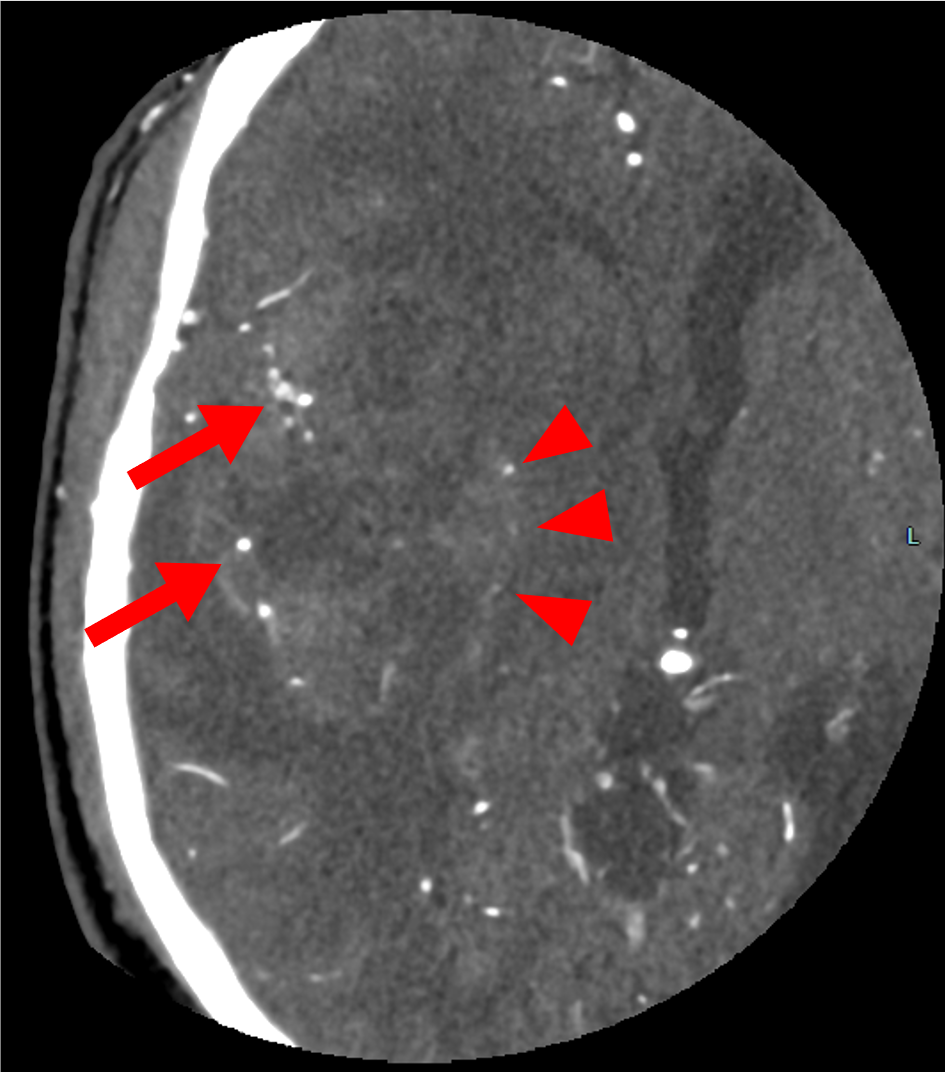

主訴は左下肢の脱力、歩行困難。右島回に5cm大の腫瘤を指摘され、膠芽腫が疑われた。術前の血管評価のため頭部CTA、CTVを施行した。

当該疾患の診断における造影CTの役割

島回部のglioblastomaの術前CTAにおいて、手術中の予期せぬ血管損傷の回避、ひいては術中出血や虚血性合併症のリスク低減のために中大脳動脈や穿通枝など主要血管を可視化する必要がある。血管と腫瘍の位置関係を把握することで、腫瘍をできる限り摘出しつつも神経機能を温存する戦略を立てることができるようになる。隣接する基底核部は錐体路や感覚路と近接するため、摘出範囲の判断のために術前の血管情報が不可欠である。

また、術前の血管画像をナビゲーションシステムに統合することで、リアルタイムに血管・神経の位置を確認しながら手術が進められ、より手術の安全性を高めることができる。膠芽腫は浸潤性が強いため、血管を温存しながらも腫瘍を完全に摘出することが困難であることが多く、機能温存と腫瘍制御の最適なバランスのために術前の詳細な血管描出が重要となる。

術前における頭部血管描出、特に細い穿通枝を十分に描出するため、動脈内のCT値を十分に上昇させることが不可欠であり、これはVR画像の作成においても重要な要素となる。そのため、なるべく高濃度のヨード造影剤を選択し、高容量を急速静注することが推奨される。さらに、生理食塩水で後押しを行うことでルート内や静脈内に残存した造影剤をフラッシュし、ボーラス性を高めることができる。加えて、低管電圧での撮影は血管内CT値の上昇に寄与し、描出能をさらに向上させる。

一方、頭部は静脈構造が複雑であるため、撮影タイミングが遅れると動脈の正確な評価が困難となる。したがって、脳静脈が描出される前に純粋な動脈相を取得することが極めて重要であり、造影される腫瘍病変と動脈を識別する上でも撮像のタイミングは大きな意味を持つ。実際の撮影ではボーラストラッキング法が簡便かつ汎用性の高い手法として多くの施設で用いられており、総頚動脈や中大脳動脈近位部でCT値をモニタリングし、一定の閾値を超えた時点で撮影を開始することが一般的である。画像処理に関しては、できる限り薄いスライスを用いることで評価の精度を高め、VR画像による立体的な血管走行の把握も重要となる。